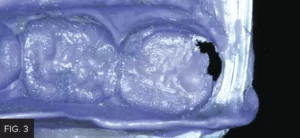

The remaining restoration was then removed from the impression using a bur in order to provide room for a full thickness temporary. It was necessary to perforate the temporary impression in order to gain sufficient space. (FIG. 3)

The areas of the missing crown structure were removed with a rotary instrument. It is important that sufficient material is removed to allow for adequate thickness of temporary material.